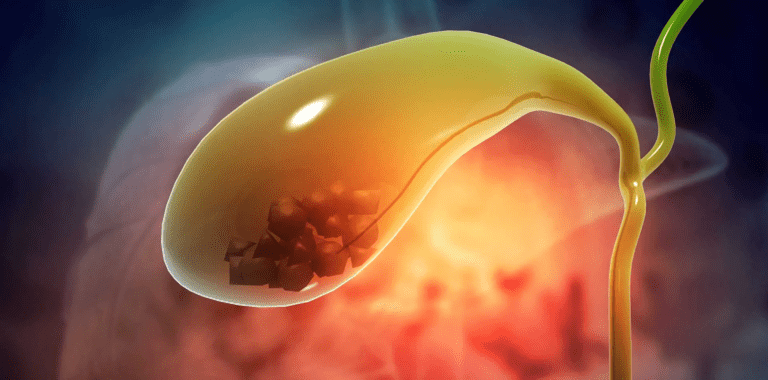

Gallstones